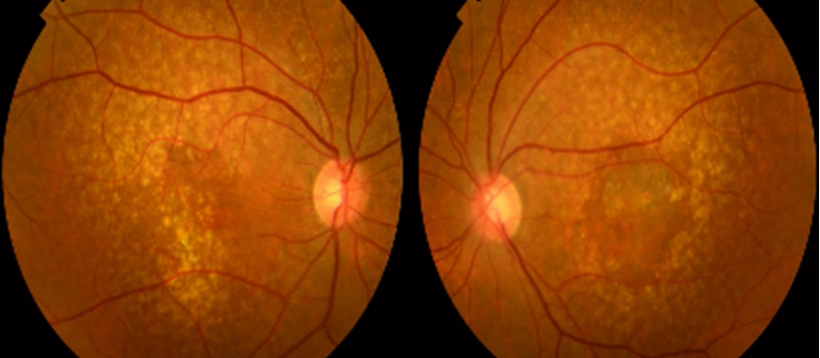

OCT能够更清晰地显示表皮玻璃疣对视网膜色素上皮的破坏,是诊断表皮玻璃疣和监测其进展的关键工具。表皮玻璃疣的OCT分型:1型,视网膜色素上皮基底膜浅层隆起,内容物难以分辨;2型,三角状隆起伴"锯齿状"外观,内部低反射;3型,色素上皮基底层圆顶状宽基底隆起(图8)。

图片

图8.OCT显示的表皮玻璃疣表型。1型模式的特点是视网膜色素上皮浅层隆起(上图)。2型模式表皮玻璃疣呈角状隆起伴“锯齿状”外观(中图)。3型表皮玻璃疣表现为色素上皮基底膜丘状隆起(下图)。